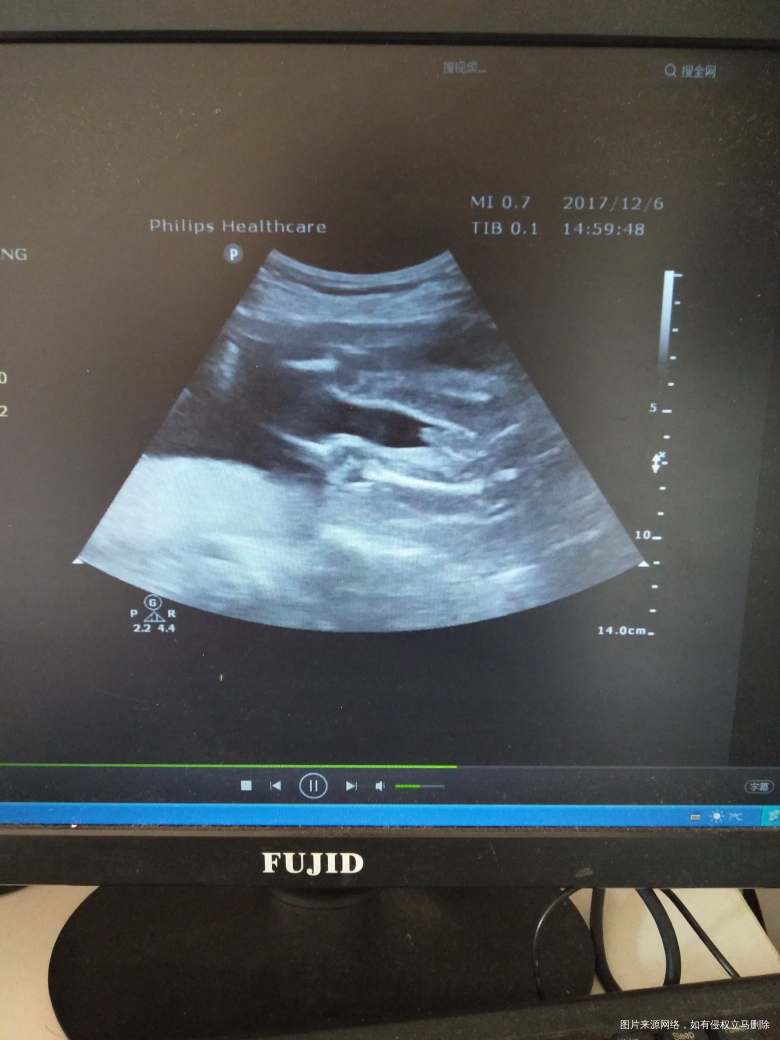

有宝宝的性器官图片 只是我还看不懂?有经验的宝妈可以帮我看一下

吗?

男孩吧

男孩

男宝吧,好清楚

像男孩

小鸡鸡好明显[大笑]